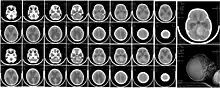

| CT scan, showing a tumorous mass in the posterior fossa, giving rise to obstructive hydrocephalus, in a six-year-old girl | |